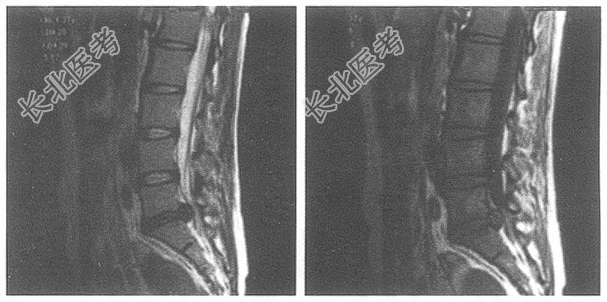

- 单项选择题女,37岁。腰腿痛半年, 结合图像,选择最佳选项

A、L5~S1椎间盘变性

B、L5~S1椎间盘向后突出

C、L5~S1椎间盘变性并向后突出

D、L5~S1椎间盘膨出

E、L₄₋₅椎间盘向后突出